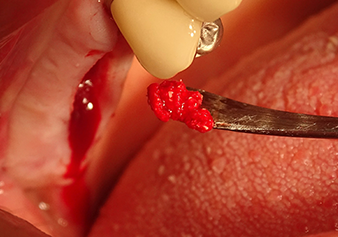

Подготовка ложа имплантата и наращивание

После промежуточного контроля (рис. 4) был проведен еще один этап подготовки (рис. 5). За тем, с помощью гидравлического инструмента Z35P мембрана была поднята в нужное положение (рис. 6 и 7). Далее, следовала дальнейшая пьезохирургическая подготовка ложа для имплантата, завершенная с помощью ротационного бора и лопаточной фрезы до диаметра имплантата 4,8 мм. Перед установкой имплантата под мембрану Шнейдера был введен аугментационный материал (размер частиц около 0,8-1,6 мм) (рис. 8).